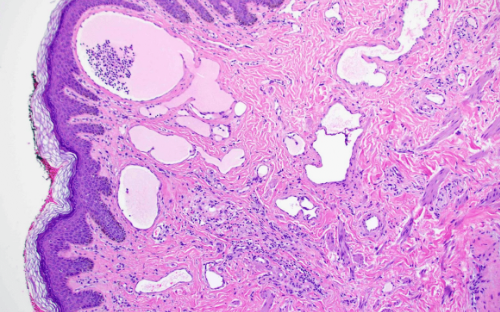

DERMATOHISTOPATHOLOGY:

On histopathologic examination, present within the dermis are an increased number of dilated vascular spaces filled with lymph.